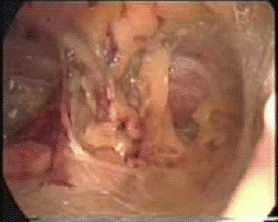

Рис. 7. Содержимое грыжевого мешка - петля тонкой кишки (Surgical Endoscopy, Hernia Treatment)